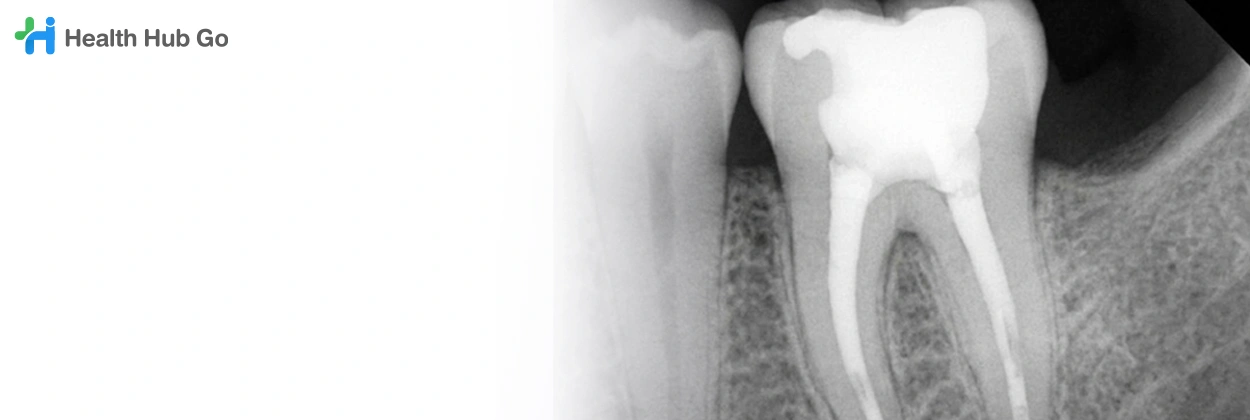

Periapical Dental X-ray